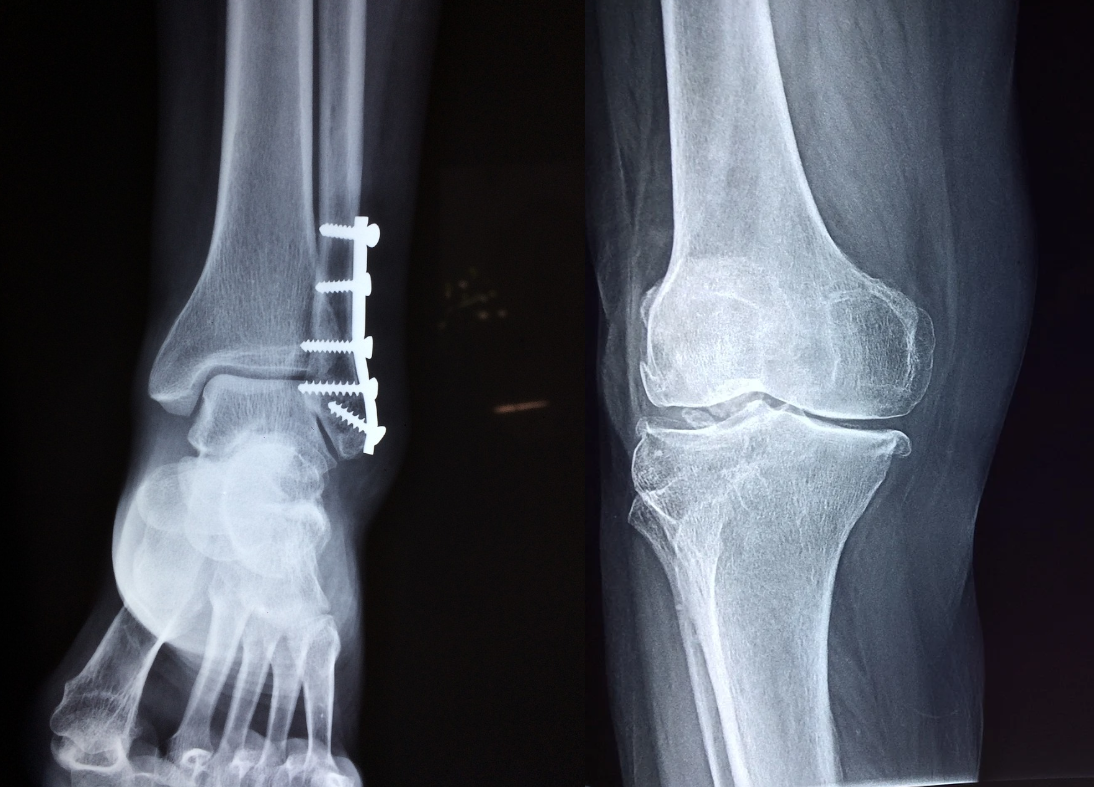

I tu także mamy możliwość otwarcia stawu, nastawiania i zespolenia głowy kości udowej z szyjką (łącznikami w postaci drutów i śrub). Stabilizacja trwa do momentu zakończenia wzrostu w obrębie głowy kości udowej, czyli do czasu zrośnięcia się chrząstki nasadowej głowy kości udowej. Kiedyś nie robiło się takich zabiegów, po prostu takie osoby chodziły z nogą skierowaną na zewnątrz (skutek przemieszczenia się głowy kości udowej), a zdeformowane biodro szybko ulegało zniszczeniu z koniecznością wczesnej endoprotezoplastyki. Dziś deformację taką możemy skutecznie skorygować.